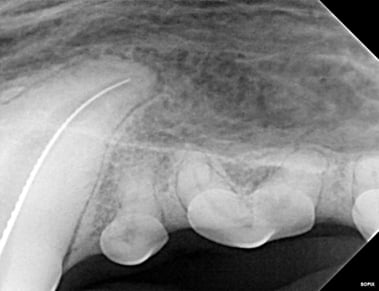

Below: During RCT - Radiograph finding working length to clean and measure canal

%20-%20March%202024/during%20RCT%20-%20finding%20working%20length.jpg?width=379&height=291&name=during%20RCT%20-%20finding%20working%20length.jpg)

Below: During RCT - finding master file size to clean canal walls appropriately and find master cone size of gutta percha

%20-%20March%202024/Radiograph%20of%20master%20file%20during%20RCT.jpg?width=386&height=296&name=Radiograph%20of%20master%20file%20during%20RCT.jpg)